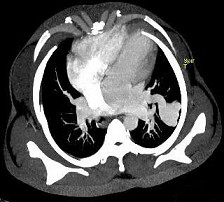

男性,26岁,头晕、气逼三年余,CT检查如图所示,请选择的最可能诊断 ( ) XN-27051.jpg XN-27052.jpg XN-27053.jpg XN-27054.jpg

题型: 单选题 分类: 心血管内科

• D.动静脉畸形